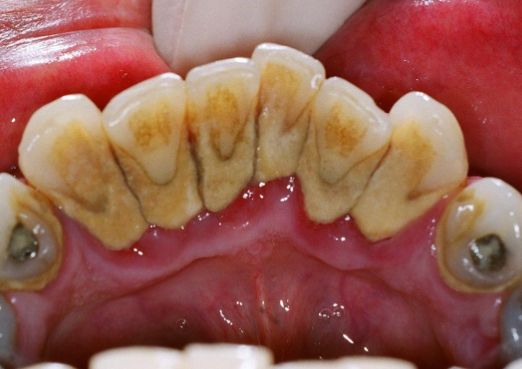

牙齿磨合力过大也会造成牙龈萎缩,牙龈底部结石会引发牙龈萎缩等,这些都会引发牙龈萎缩的发生。

牙根处的牙结石